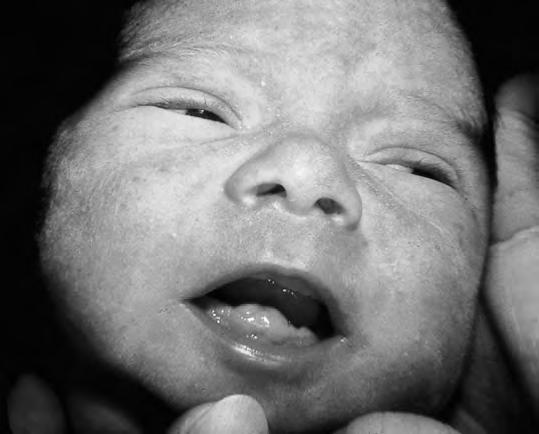

Características de la piel

En la cara (zona de la raíz de la nariz, párpados y frente) y a veces en el occipucio, son frecuentes pequeñas dilataciones telangiectásicas (angiomas capilares o planos) denominadas nevi materni. Suelen enrojecer al llorar el niño y palidecer progresivamente, hasta desaparecer hacia el final del primer año. Es frecuente encontrar, sobre todo en las alas de la nariz, unos elementos puntiformes y amarillentos, como pequeños quistes sebáceos (millium facial) (Fig. 2.1.2) que desaparecen espontáneamente al segundo o tercer mes. Asimismo, a menudo aparecen a los pocos días de vida lesiones puntiformes de acné neonatorum, relacionadas con la crisis hormonal. Las lesiones son mayores y más dispersas que, en el caso del millium, tienen ligera reacción inflamatoria y curan en el plazo medio de 8-10 días. En la región sacra y nalgas existe, a veces, una mancha de color pizarroso que puede llegar a ser muy extensa, que desaparece a menudo hacia el primer año pero que en el lactante puede llevar a la confusión con hematomas: es la mancha de Baltz y, en general, está en relación con la pigmentación racial de la piel. Si se detectan manchas de color café con leche harán sospechar una neurofibromatosis, cuando aparecen más de tres a esta edad. En algunos casos pueden surgir ampollas de succión en manos o pies por succión bucal en el periodo fetal; en muchos casos se observa la ampolla rota y queda la lesión residual redondeada. Las manchas acrómicas son sugestivas de esclerosis tuberosa.